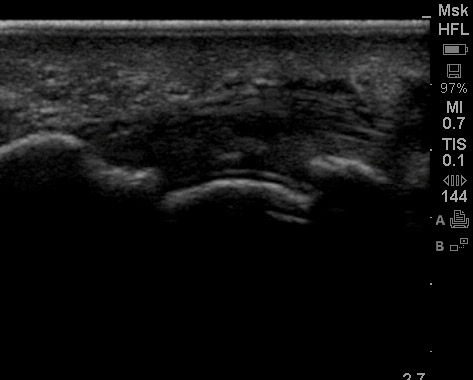

Whilst pondering this dilemma I do what I usually do – ultrasound!

Really I am just having a gander to check where I could place a needle into a pocket of synovial fluid safely. This is an image I caught…. It contains a sign which is supposedly very specific for one of the above diagnoses. Maybe we can spare the needle?

Can you tell me what the sonographic sign is? And which differential does it suggest?

That looks like the double contour sign of gout, but I still don’t think you can rule out septic arthritis with that picture (superimposed infection of an already abnormal joint).

Ultrasound pic looks like a baby Darth Vader.